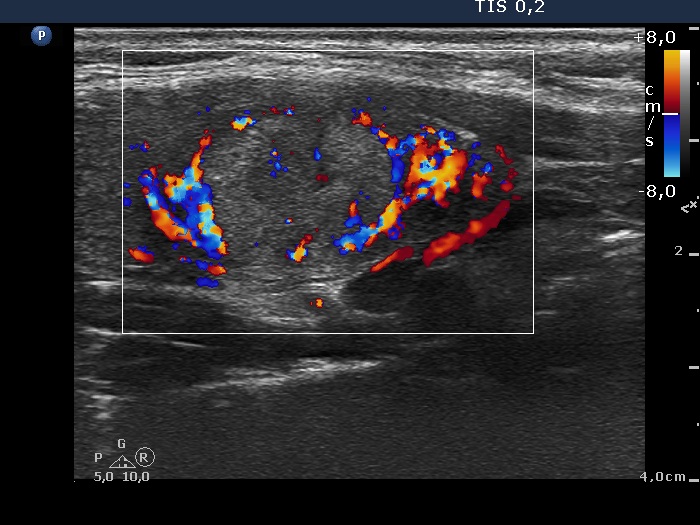

Benign nodular hyperplasia - Case 53. (ultrasonographic picture 6)

Right lobe, longitudinal scan

Lower part of the right lobe, longitudinal scan. The hyperechogenic nodule presents presents partly perinodular vascularity.